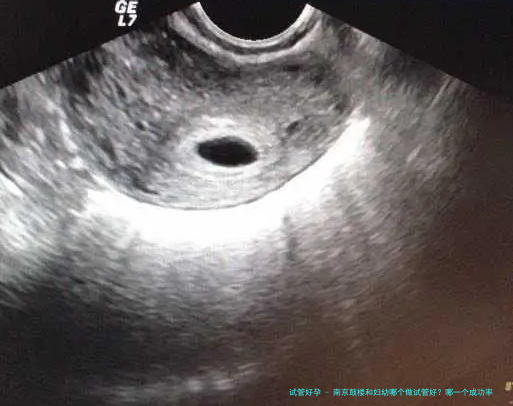

⑴囊胚移植:根据研究,囊胚移植的着床概率高于保存胚胎。所以我们可以在胚胎移植中进行有针对性的囊胚移植,前提是患者拥有高质量的胚胎和优秀的子宫环境,这将大大增加胚胎移植的几率。